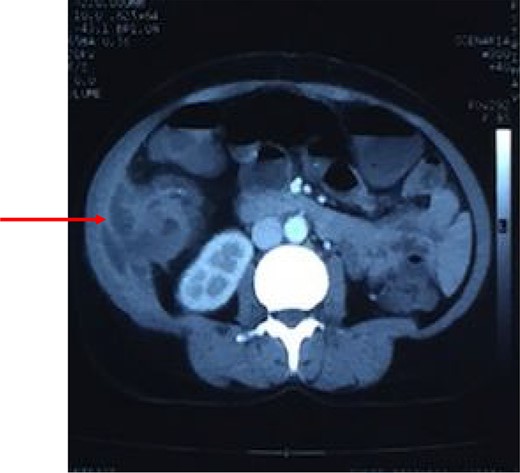

Computed tomography of the abdomen showing perforation of the tumor through muscles of lateral abdominal wall with abscess formation as seen on CT scan.

After resuscitation with intravenous fluids, administration of broad-spectrum intravenous antibiotics and intravenous analgesics, a contrast-enhanced computed tomography (CECT) scan was done to further characterize the lesion. CECT of abdomen showed large abscess extending from the subcutaneous and intermuscular planes over the right iliac fossa and breaching the peritoneum. It showed heterogeneous wall thickening of the proximal part of the ascending colon with loss of mural stratification and causing luminal narrowing, measuring 4.8 × 5.1 × 4.5 cm with surrounding inflammatory changes with adjacent well-defined collection 11.3 × 4.5 × 10.9 cm and few air pockets and infiltrating the right lower abdominal wall (Fig. 2). Pus aspirated from the right abdominal swelling and was sent for culture and sensitivity. Patient was taken up for diagnostic laparoscopy and proceeded.